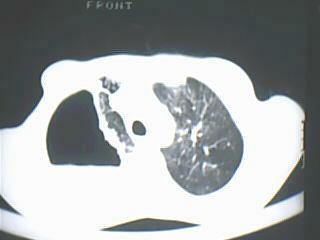

以下是引用随光逐影在2009-8-7 15:40:00的发言:[br]考虑右肺继发性肺结核并右肺上叶空洞形成,两肺支气管播散;不排除右肺上叶空洞内霉菌感染可能。

以下是引用jiangjing在2009-8-7 14:38:00的发言:[br]右上肺张力空洞,酐珞坏死灶,支气管扩张,多发播散灶,纵膈淋巴结显示,胸膜增厚---结核